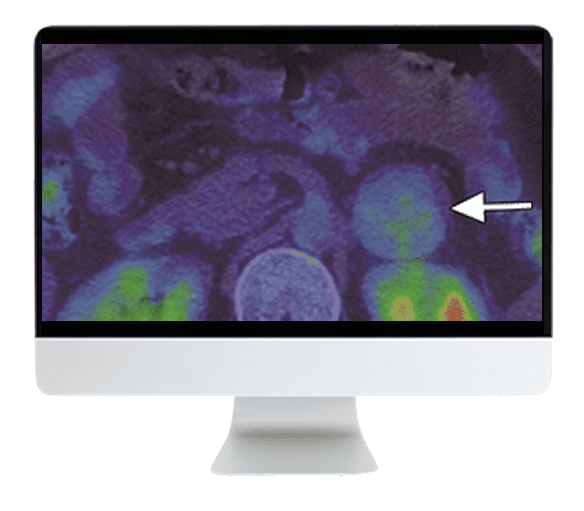

With the completion of several large clinical trials in nuclear medicine leading to significant breakthroughs for both dementia and cancer patients, this Online Course highlights PET imaging of proteinopathies for neurodegenerative disease, amyloid PET for dementia, FES-PET for breast cancer, as well as updates to treatments such as PRRT and Radium-223.